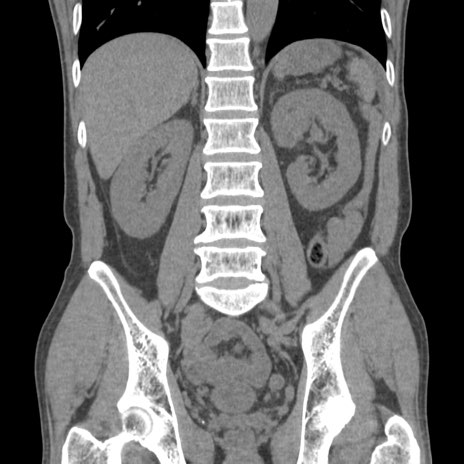

症例56 CT(冠状断像)